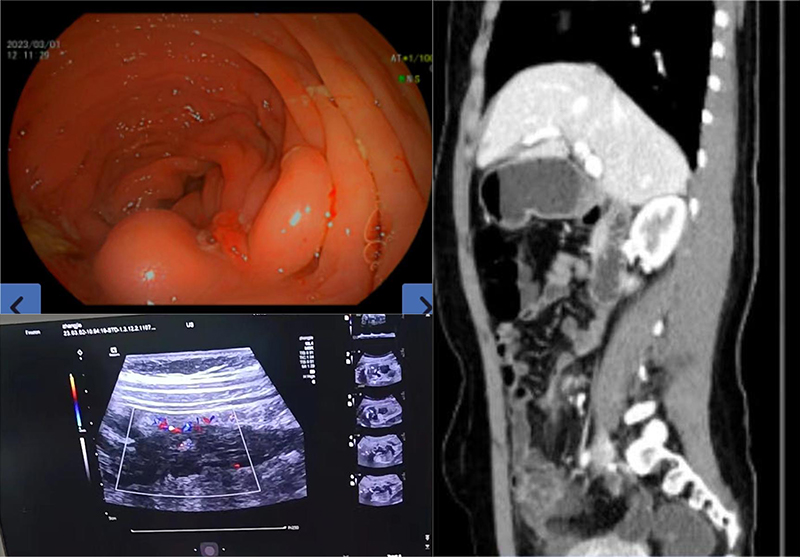

3月2日,中南大学湘雅三医院消化内科联合超声科成功完成一例克罗恩病(CD)患者肠道超声检查(IUS)。患者经检查,评估因肠腔狭窄内镜不能通过的肠腔,发现影像学未明确的腹腔小脓肿,明确患者肠腔狭窄的性质。该检查的顺利实施,为患者后续的治疗决策提供重要的依据。目前国内仅有少数医院能够顺利开展该项检查。

该患者为一位年轻女性,患克罗恩病4年,行生物制剂维持治疗,症状控制稳定。此次定期复查发现大便隐血阳性,炎症指标增高,进一步行肠镜检查,发现回盲部肠腔狭窄并溃疡形成,内镜不能通过狭窄处对病灶进行全面评估。消化内科主任王晓艳教授、副主任田力副教授充分了解患者病情后,消化内科炎症性肠病团队联合超声科高峰教授为患者完成经腹肠道超声检查,全面评估肠腔狭窄处肠管壁及肠外情况,发现患者影像学未明确的肠管周围的小脓腔,超声造影考虑患者肠腔狭窄以纤维化为主。通过多学科会诊(MDT)讨论后,制定了先外科手术切除狭窄肠管再药物维持治疗的方案,通过肠道超声检查,结合患者内镜、影像学及炎症指标,调整及优化了该患者的治疗决策,制定了最佳的诊疗方案。